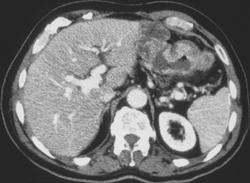

Otherwise Normal Stomach With Subtle Gastric Tumor (adenocarcinoma)